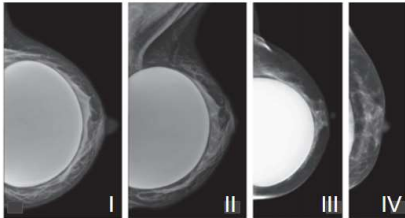

“A chance de se ter uma neoplasia mamária invasiva durante a vida, varia com a idade, etnia e dados geográficos, culturais e socioeconômicos. De uma maneira geral, a estimativa é de que aproximadamente 12,3% das mulheres serão diagnosticadas com câncer de mama em algum momento ao longo de sua vida.” Análise a figura e as posições representadas (I, II, III e IV) e assinale a alternativa incorreta.